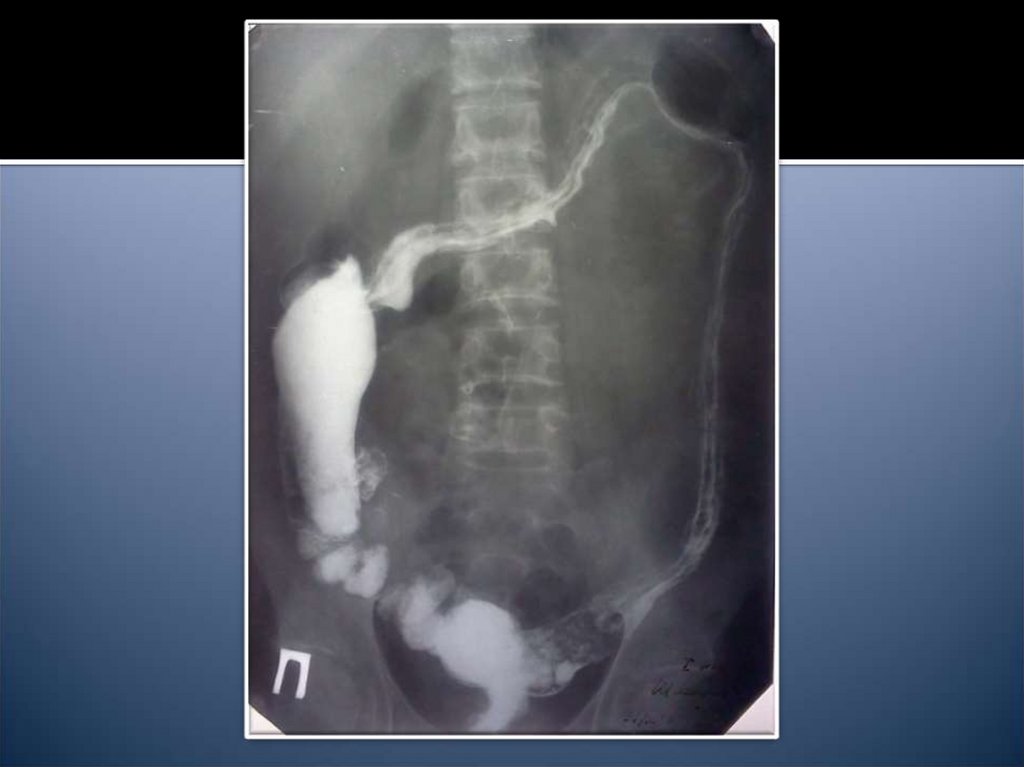

14. Рентгенологические признаки

Чаши Клойбера

Симптом Кивуля (аркады)

Проба Шварца

Пневматоз петель кишечника